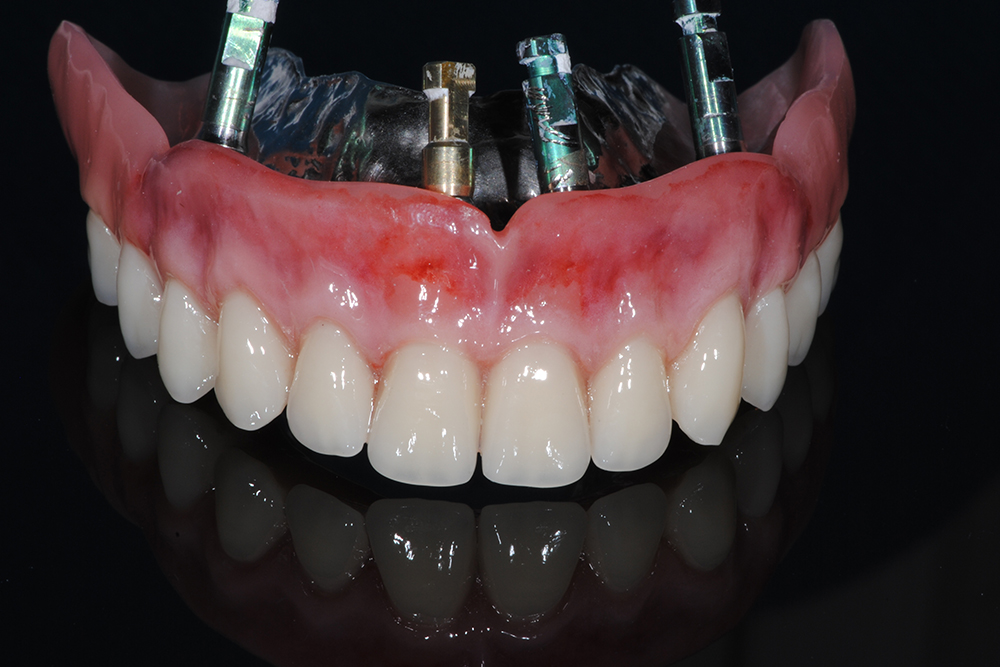

Ripristino dell’arcata superiore ed inferiore su overdenture su barra